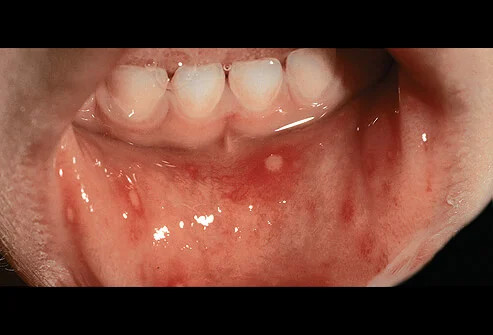

- Adanya lesi menyakitkan berwarna merah seperti melepuh di lidah, gusi dan bagian dalam pipi

Periode infeksi hingga timbul gejala berkisar 3-6 hari, di mana demam menjadi pertanda pertamanya. Setelah demam selama 1-2 hari, luka yang menyakitkan mulai berkembang di mulut atau tenggorokan diikuti dengan ruam pada tangan dan kaki atau bokong.

Ketika timbul lesi pada lidah atau gusi, anak-anak cenderung menolak makan dan minum sehingga orang tua harus mencari cara agar anak tetap tercukupi kebutuhan cairan dan tidak sampai dehidrasi.